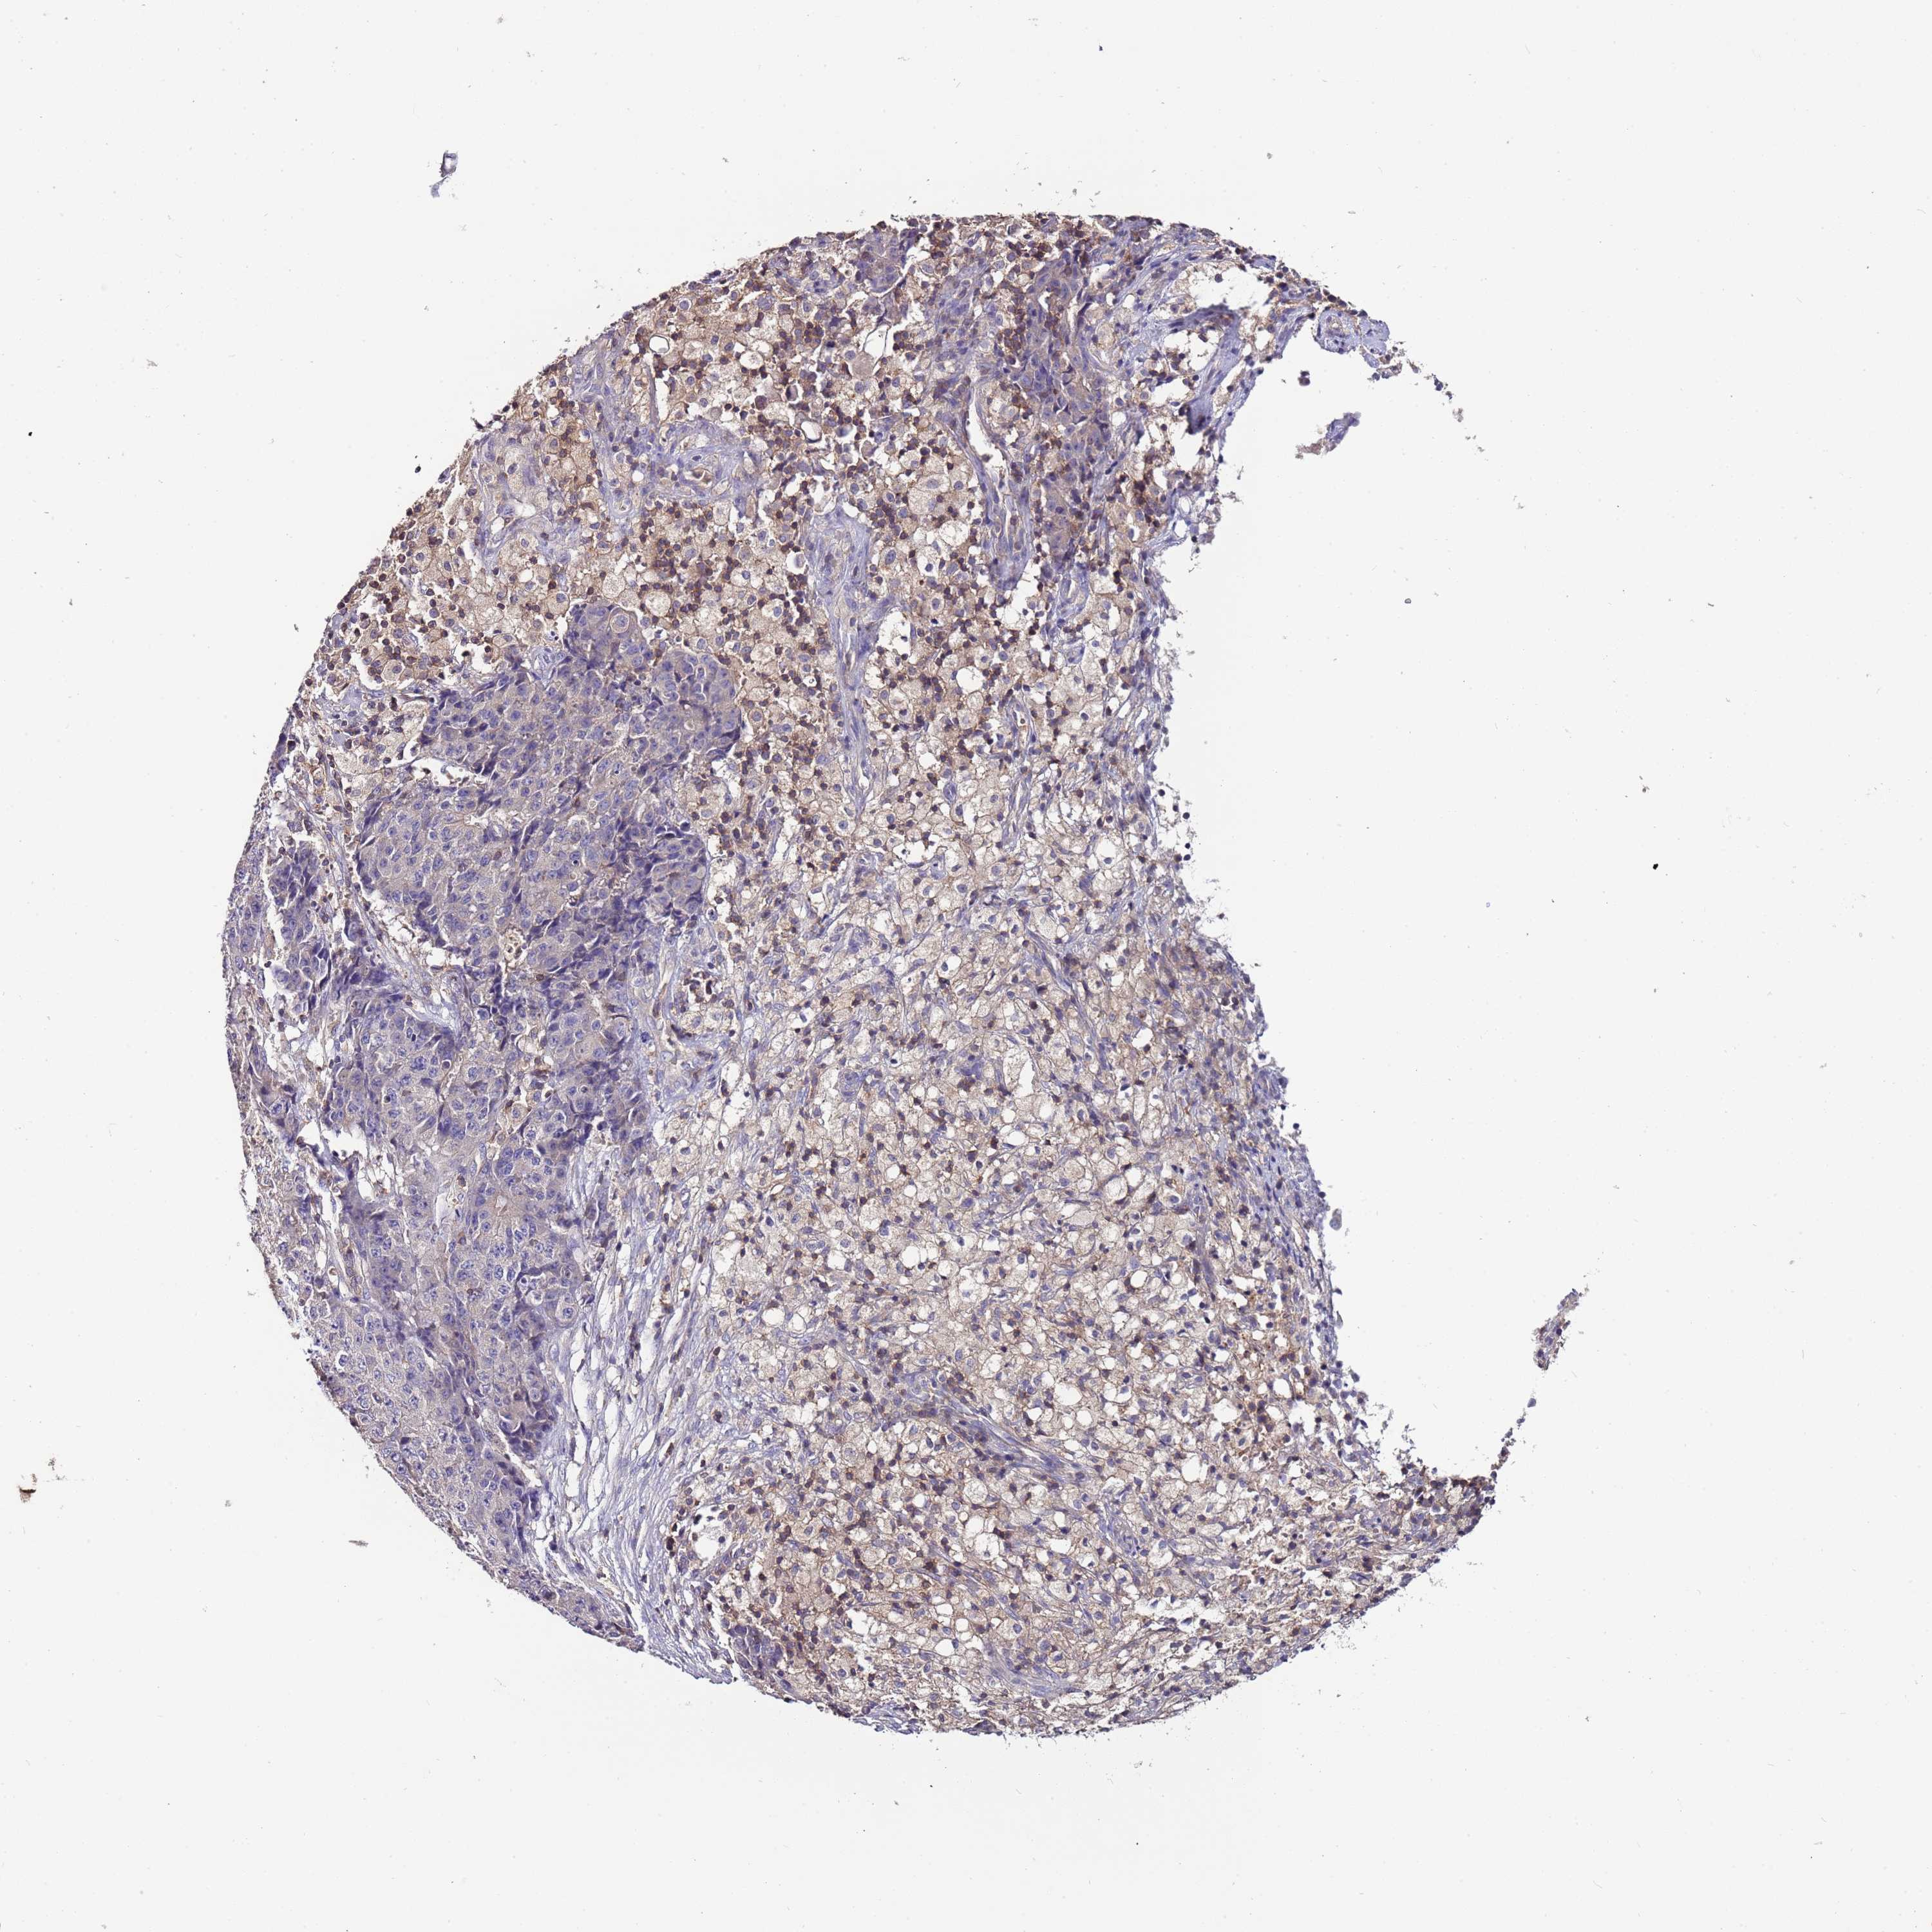

OVARIAN CANCER - Protein expressioni

A mouse-over function shows sample information and annotation data. Click on an image to view it in a full screen mode. Samples can be filtered based on level of antibody staining by selecting one or several of the following categories: high, medium, low and not detected. The assay and annotation is described here.

Note that samples used for immunohistochemistry by the Human Protein Atlas do not correspond to samples in the TCGA dataset.

Antibody stainingi

Antibody staining in the annotated cell types in the current human tissue is reported as not detected, low, medium, or high, based on conventional immunohistochemistry profiling in selected tissues. This score is based on the combination of the staining intensity and fraction of stained cells.

Each image is clickable and will lead to virtual microscopy that enables deeper exploration of all samples and also displays staining intensity scores, fraction scores and subcellular localization as well as patient and tissue information for each sample.

Antibody HPA048615

Staining

High

Medium

Low

Not detected

Intensity

Strong

Moderate

Weak

Negative

Quantity

>75%

75%-25%

<25%

None

Location

Nuclear

Cytoplasmic/membranous

Cytoplasmic/membranous,nuclear

Cystadenocarcinoma, serous, NOS

Carcinoma, NOS

Cystadenocarcinoma, mucinous, NOS

Carcinoma, endometroid